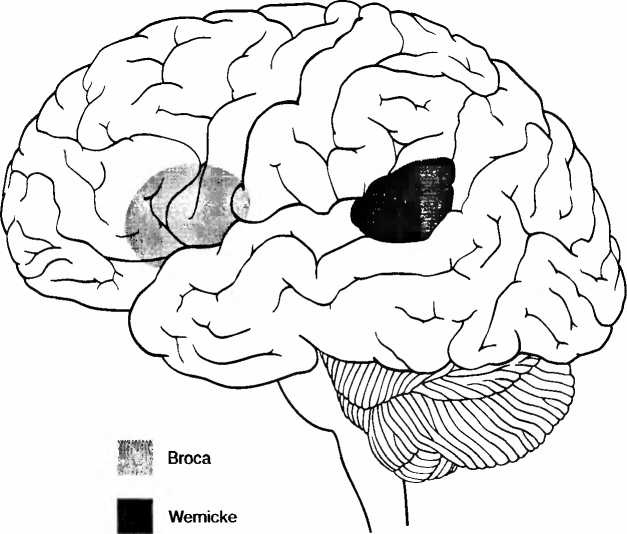

Иллюстрация к книге — Мы - это наш мозг. От матки до Альцгеймера [i_010.jpg]

Рис. 7. Речевые центры Брока (лобный, владение речью) и Вернике (височный, понимание речи). Эти центры также тесно связаны с восприятием музыки и пения. Музыка и речь очень близки друг к другу.

Наше окружение в течение первых лет после появления на свет определяет строение систем мозга, ответственных за речь. Позднее, после критического периода развития систем речи, когда мы пытаемся говорить на другом языке, в нашем мозгу уже запечатлен родной язык, и это приводит к появлению акцента. Области мозга, обрабатывающие слова и визуальную информацию, у детей 9-11 лет еще перекрывают друг друга. У взрослых происходит специализация, и оба вида информации обрабатываются в отдельных областях мозга. Языковая среда ведет к образованию неизменных различий в структурах и функциях мозга. В зависимости оттого, является ваш родной язык японским или одним из западных языков, гласные звуки и звуки животных обрабатываются в левом или в правом полушарии, вне связи с вашим генетическим происхождением. В лобной доле коры головного мозга лежит речевая зона Брока (рис. 7) Если взрослый человек учит второй язык, внутри ее используется другой субареал. Но если ребенок растет как двуязычный, оба языка используют одни и те же фронтальные области. Левое хвостатое ядро (nucleus caudatus, рис. 26) контролирует, какая именно речевая система мозга используется. Язык и культурное окружение определяют не только, какие системы мозга заняты обработкой речи, но и как именно могут интерпретироваться выражения лица; как люди привыкли, окинув взглядом, схватывать образ и то, что их окружает. Так, японцы и жители Новой Гвинеи не могут хорошо различать, выражает лицо страх или удивление, а китайцы, в противоположность американцам, сосредоточивают внимание не только на наиболее важном предмете, но рассматривают его в отношении с непосредственным окружением. При подсчете людей китайцы используют частично и другие области мозга, нежели англоговорящие люди Запада. И те и другие пользуются теми же арабскими цифрами и используют ту же нижнюю часть теменной доли коры головного мозга (рис. 1). Но англоговорящие, кроме того, больше используют речевые системы для обработки чисел, тогда как у китайцев в большей степени задействованы визуально-моторные системы. Это объясняется тем, что китайские дети растут, изучая иероглифы. Китайские счеты суаньпань больше не играют сколько-нибудь заметной роли в современном Китае.